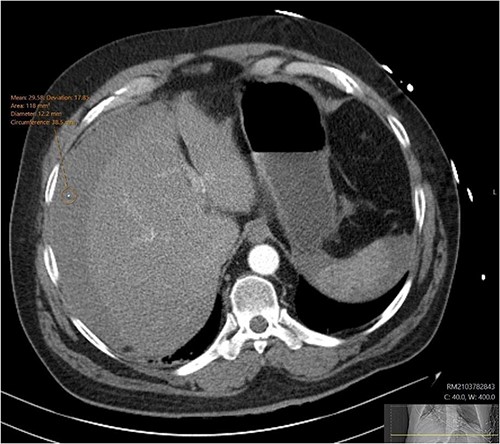

A CT abdomen-pelvis (CT-AP) revealed an acute haematoma inferolateral to the third part of the duodenum and another at the root of the mesentery. High density fluid related to the mesenteric bleed was also seen extending from the right para-colic gutter into the pelvis and in the peri-hepatic region. The patient was admitted under general surgery, stabilized with intra-venous fluid resuscitation, co-amoxiclav and metronidazole and cross matched for four units of blood. A CT-angiogram demonstrated acute haemorrhage throughout the abdomen with a 104 x 62 mm haematoma arising centrally at the level of L2 within the mesenteric fat (Fig. 1). The haematoma did not appear to originate from any specific mesenteric vessels but was related to some mid and distal jejunal loops. The angiogram also showed discontinuity when tracing the proximal and mid jejunal loops inferiorly, extensive haemorrhagic peritoneal fluid around the liver extending inferiorly (Fig. 2) and a small amount of peri-splenic haemorrhagic fluid. Curved reformatting of the angiogram revealed no abnormalities within the superior mesenteric artery (Fig. 3).

CT angiogram showing a peri-hepatic haematoma. Figure 2 is an axial section taken from the patient’s initial CT angiogram of the abdomen and pelvis. A large crescent shaped peri-hepatic haematoma is highlighted by the arrow displayed.